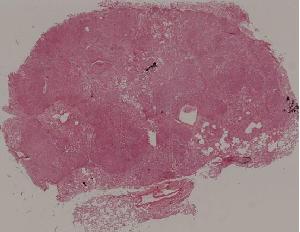

96. Pulmonary aspergillosis